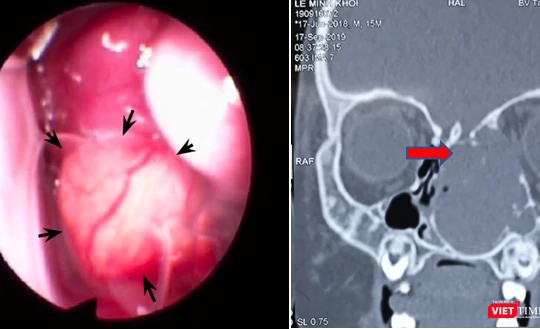

Mới 15 tháng tuổi, bé trai bị lồi mắt, nghẹt mũi vì khối u lớn chèn ép

VietTimes - Bé trai 15 tháng tuổi nhập viện trong tình trạng mắt trái bị lồi, mũi nghẹt, phải thở bằng miệng. Sau khi thăm khám và thực hiện các xét nghiệm, bác sĩ phát hiện có có khối u lớn chèn ép trong hốc mũi trái.